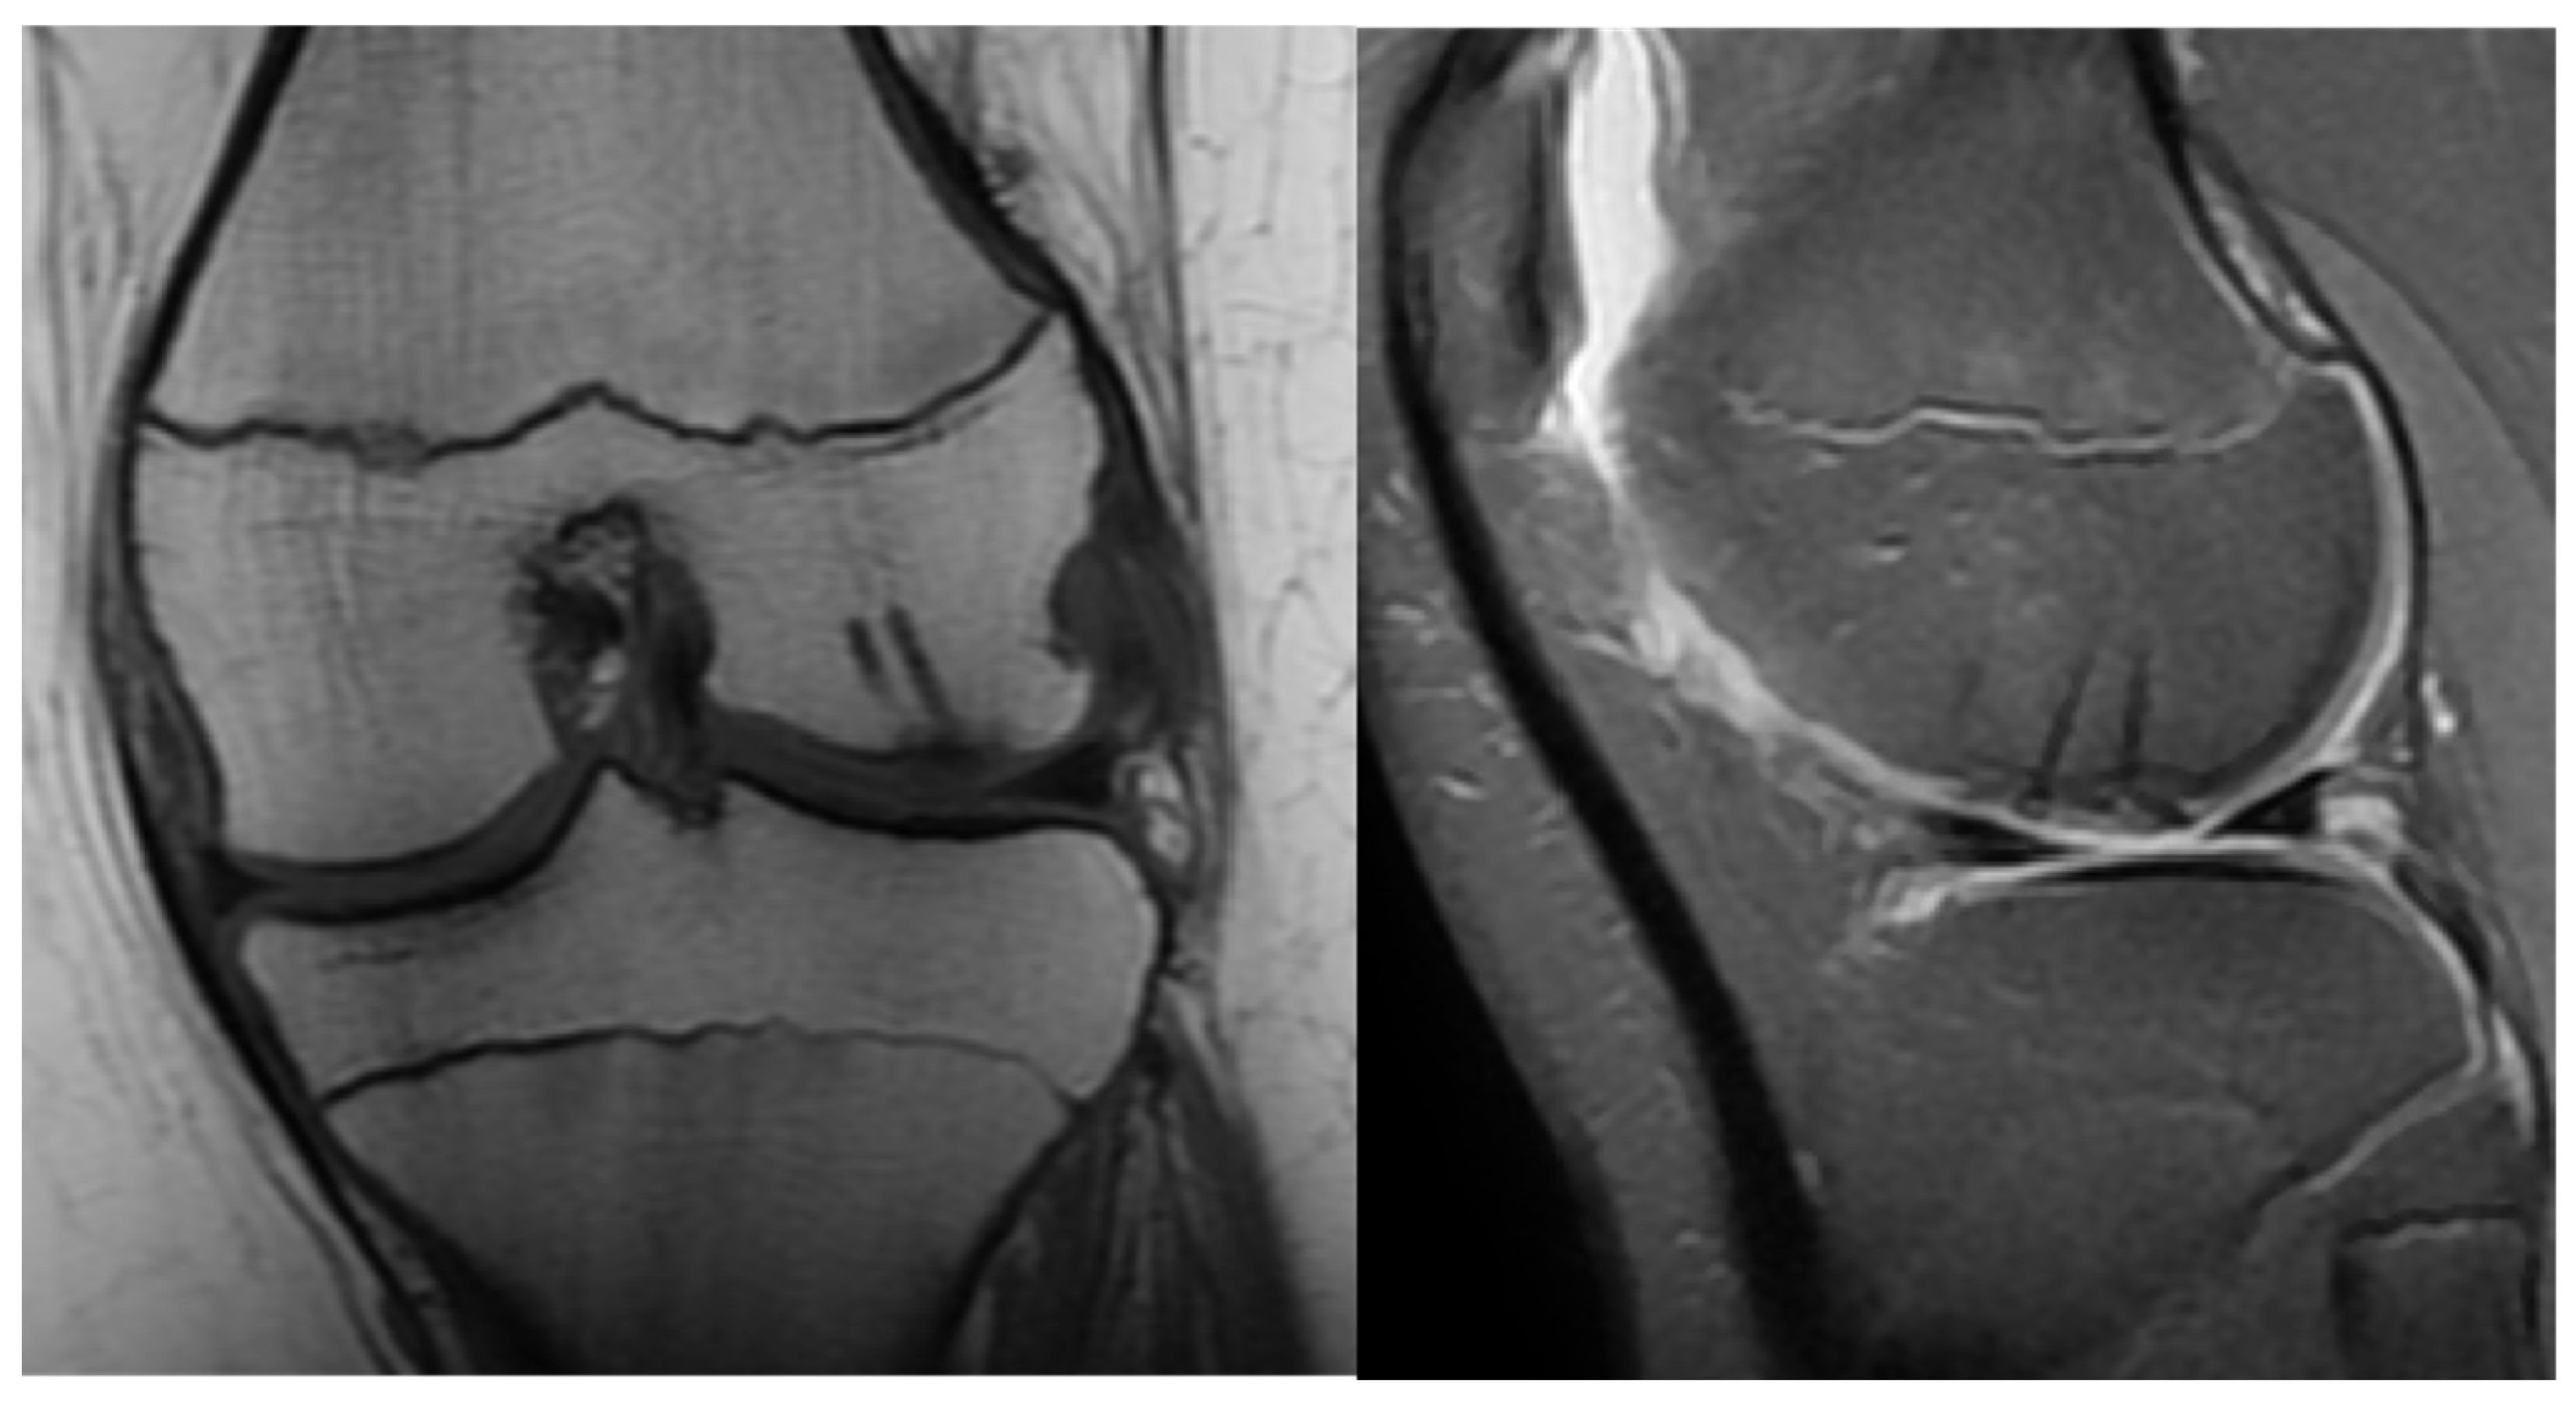

Second patient: A fifteen-year-old boy was admitted after he suffered a fall. The patient complained of pain and difficulty with weight-bearing. Knee extension was painful during the physical examination, and a hematoma could be felt in the suprapatellar bursa. Primary X-rays showed the osteochondral fracture of the patella, which was confirmed by CT imaging, with the broken piece in the lateral recess (Figure 4).

Figure 4.

CT images of the knee, showing the fragment (black arrow) and the location of the missing piece (red circle).

An arthroscopy of the right knee was performed to identify the missing piece and exclude any associated injuries. After medial arthrotomy, the patella was repositioned, and the broken piece became visible on the lateral aspect of the knee joint, in a close relationship to the tibial condyle. The fragment and patellar defect were covered by fibrin, so the coagulation was removed to yield a fresh spongious surface with the help of a Volkmann spoon.

The approximately 2 × 2 cm piece was repositioned with three 1.5 mm K-wires—a proximal, a distal and a central slightly medially—drilled until the opposing cortical surface was reached. After measurements, three 1.5 mm thick and 15 mm long absorbable nails were applied successfully for desired stability (Figure 5). The capsule and the medial patellofemoral ligament were reconstructed before complete closure with 2/0 Vicryl continuous intercutaneous suture. Swathing and elastic bandaging took place before the application of a brace, in a 15-degree position.